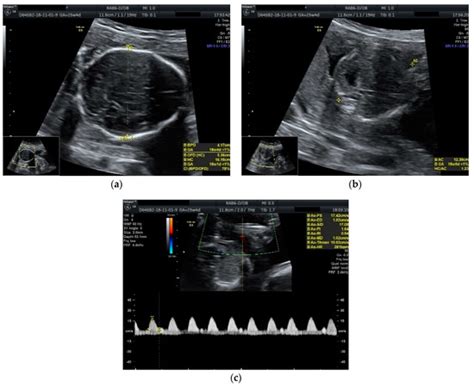

Single Fetal Demise in Twin Pregnancy—A Great Concern but Still a ...